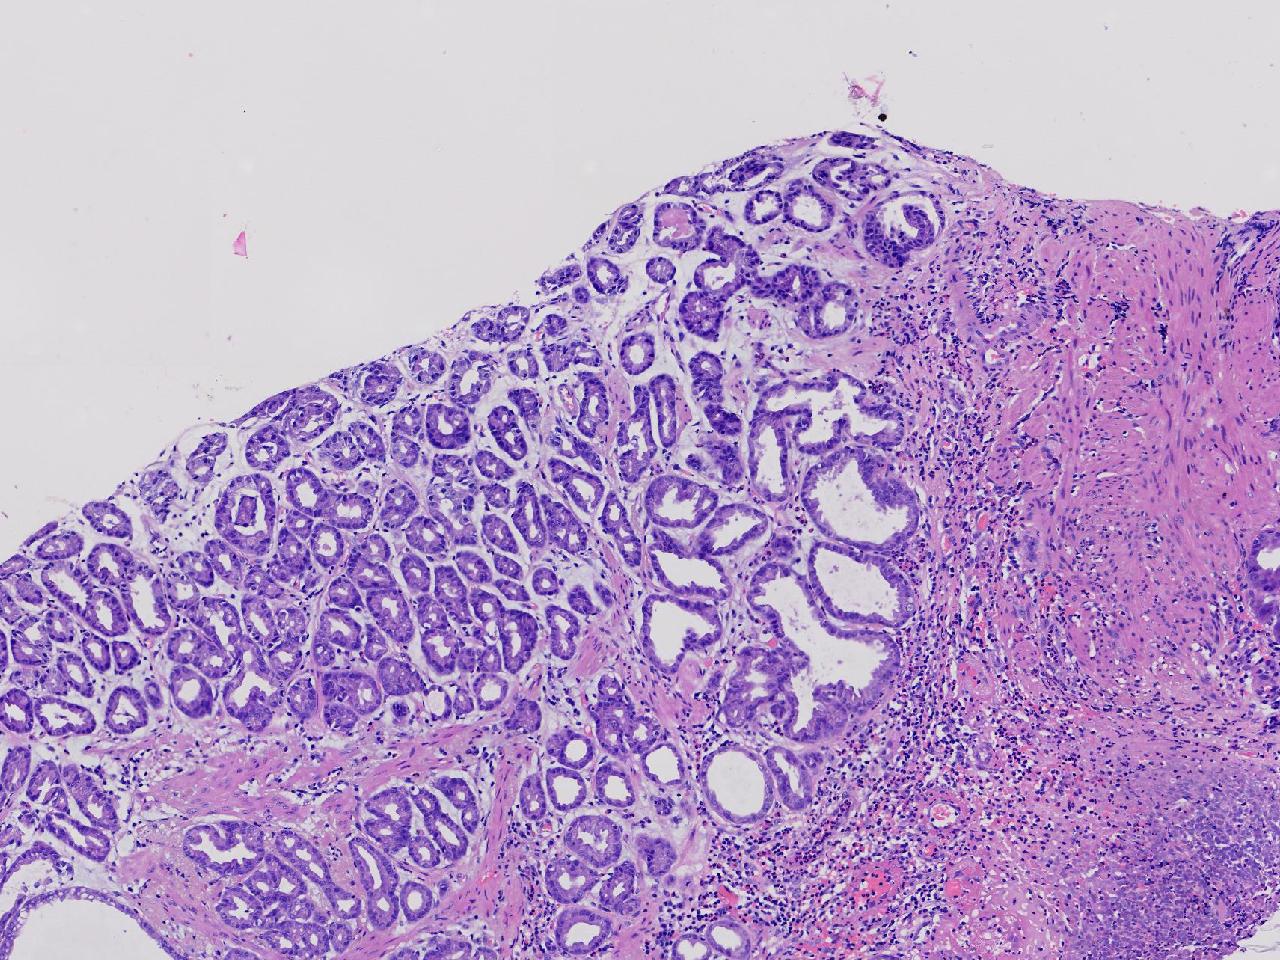

胃体上部见一大小约2厘米的溃疡灶,表覆白苔,周边充血,水肿明显,活检3块。

胃体活检

灰白色不整形软组织3块,直径均0.2厘米。

深在性囊性胃炎,少量溃疡组织

深在性囊性胃炎伴溃疡